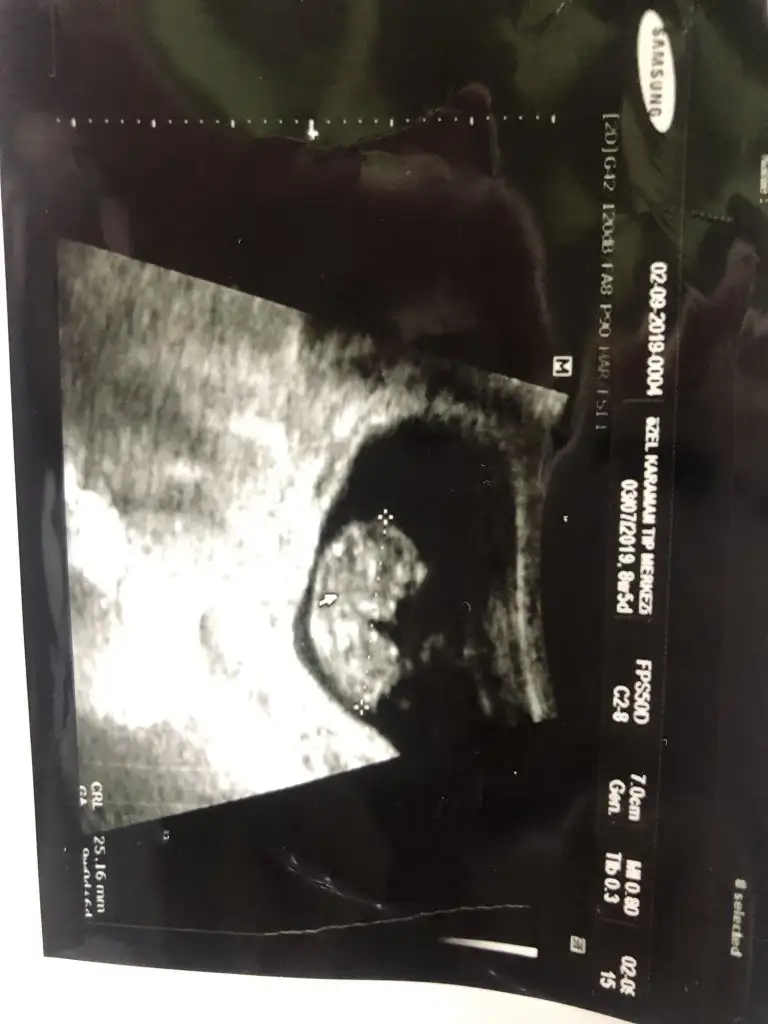

biri erkek gibi görünüyor dediler biri kız tabi net değil

Inan ki ben mesajı okumadan sadece Usg ye göre yorum yaptım ikizler miş Allah hayırlı etsin bir tanesini erkeğe benzettim diğeri net degil tek bebek iki usg zannettimbiri erkek gibi görünüyor dediler biri kız tabi net değil

Bence de kız Canım sağlıkla gelsin bize de nasip olsun inşallahKızlar merhaba size sıcak sıcak bir ultrason doktor kıza benzettim dedi yorumlarınz benim için önemli 10 haftalık

Dr erken tahmin etmiş 10. Haftalarda iki tarafa benzer nub 13 haftada nub degişmiş olur .yani cinsiyeti tam anlaşılır .inşallah gönlundeki gibi kızdır şimdilik kafa yapısı kız diyorum 11 yada 12 hafta paylaşınKızlar merhaba size sıcak sıcak bir ultrason doktor kıza benzettim dedi yorumlarınz benim için önemli 10 haftalık